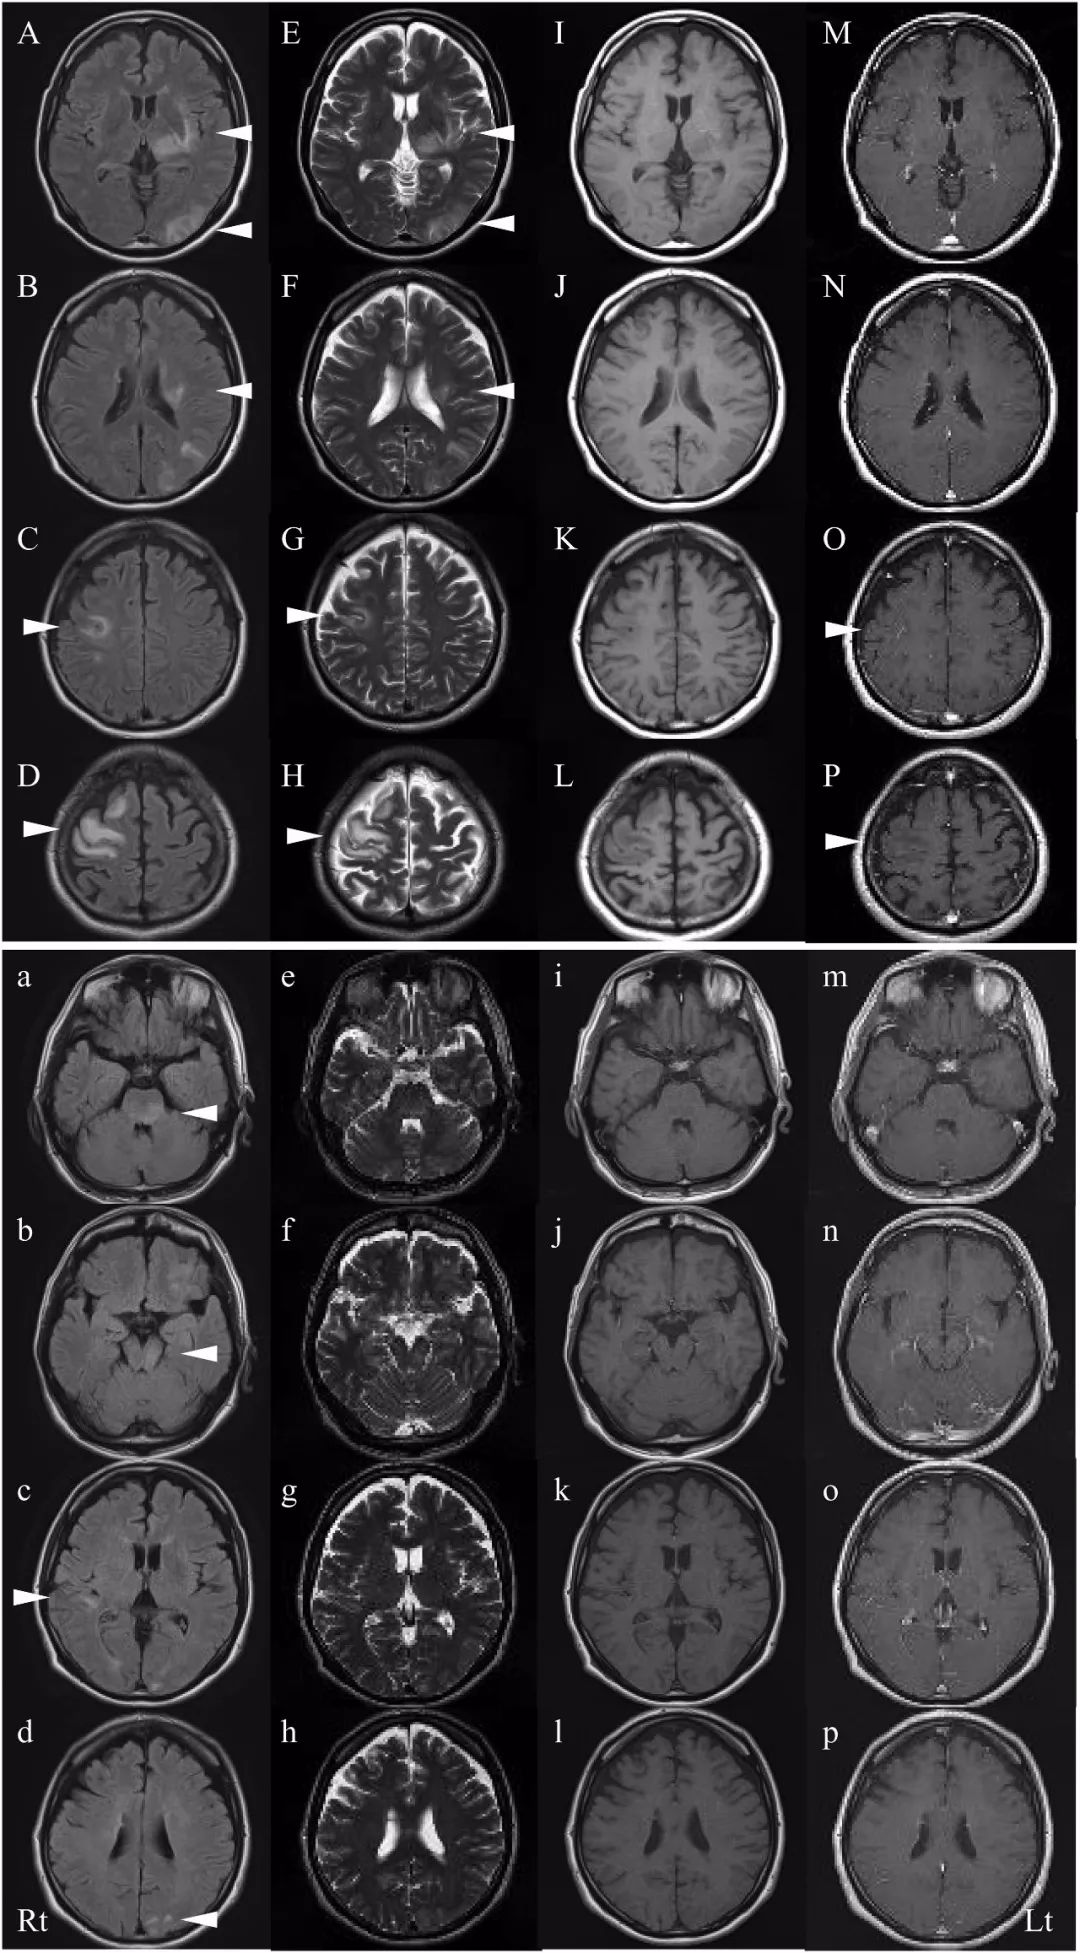

头颅MRI T2WI和FLAIR图像显示右侧额叶、左顶枕叶皮层下白质、双侧海马旁回、左侧丘脑、左侧外囊和左侧放射冠多个高信号病灶;右额叶病灶轻度增强(图1,

上图)。脊柱MRI未见明显异常。CSF分析显示白细胞略有升高(12个细胞/ ml;91%为单核细胞,9%多形核白细胞),蛋白质升高(47mg/ dL)和葡萄糖正常(58mg / dL)。感染性中枢神经系统(CNS)疾病、胶原病和血管炎的检查未见明显异常。人白细胞抗原(HLA)类型为B51:01:01.54:01。眼科检查未发现明显异常。皮肤科检查除*疮痤**外未见明显异常。鉴于对包括NBD在内的炎症性CNS疾病的考虑,患者接受了两个疗程的高剂量IV甲基强的松龙(HIMP)治疗并完全康复,于2011年5月出院。

2012年4月,患者出现头痛、咽痛和发烧并为此就诊。体格检查显示口腔复发性口腔溃疡,神经系统检查显示左上肢和下肢出现小脑性共济失调。T2WI和FLAIR显示右颞叶、左额叶、左枕叶、左侧脑桥、左侧中脑和左侧小脑中脚高信号病变(图1,下图)。CSF分析显示白细胞升高(31个细胞/μl;86%单核细胞,14%多形核白细胞),蛋白质升高(56mg / dl),葡萄糖正常(66mg/ dl)和白细胞介素-6升高(IL-6)(245pg/ml,正常<4.0pg/ ml)。怀疑NBD复发,再次给予HIMP并康复出院。口服泼尼松龙维持10mg /d,此后未观察到复发。2018年,我们对患者血清检测显示抗AQP4抗体阴性,抗MOG抗体阳性。

图1 中头颅MRI扫描显示右额叶、左顶枕叶皮层下白质、双侧海马旁回、左侧丘脑、左侧外囊和左侧放射冠多发病灶,FLAIR(AD)和T2WI(EH)呈稍高信号;T1WI稍低信号(I-L)。右侧额叶病变(M-P)中观察到轻度增强。(下图)复发时FLAIR序列(ad)和T2WI(eh)显示右侧颞叶、左侧额叶、左枕叶、左脑桥、左中脑和左侧小脑中脚高信号病灶,T1WI未见明显增强(i-p)。

图1